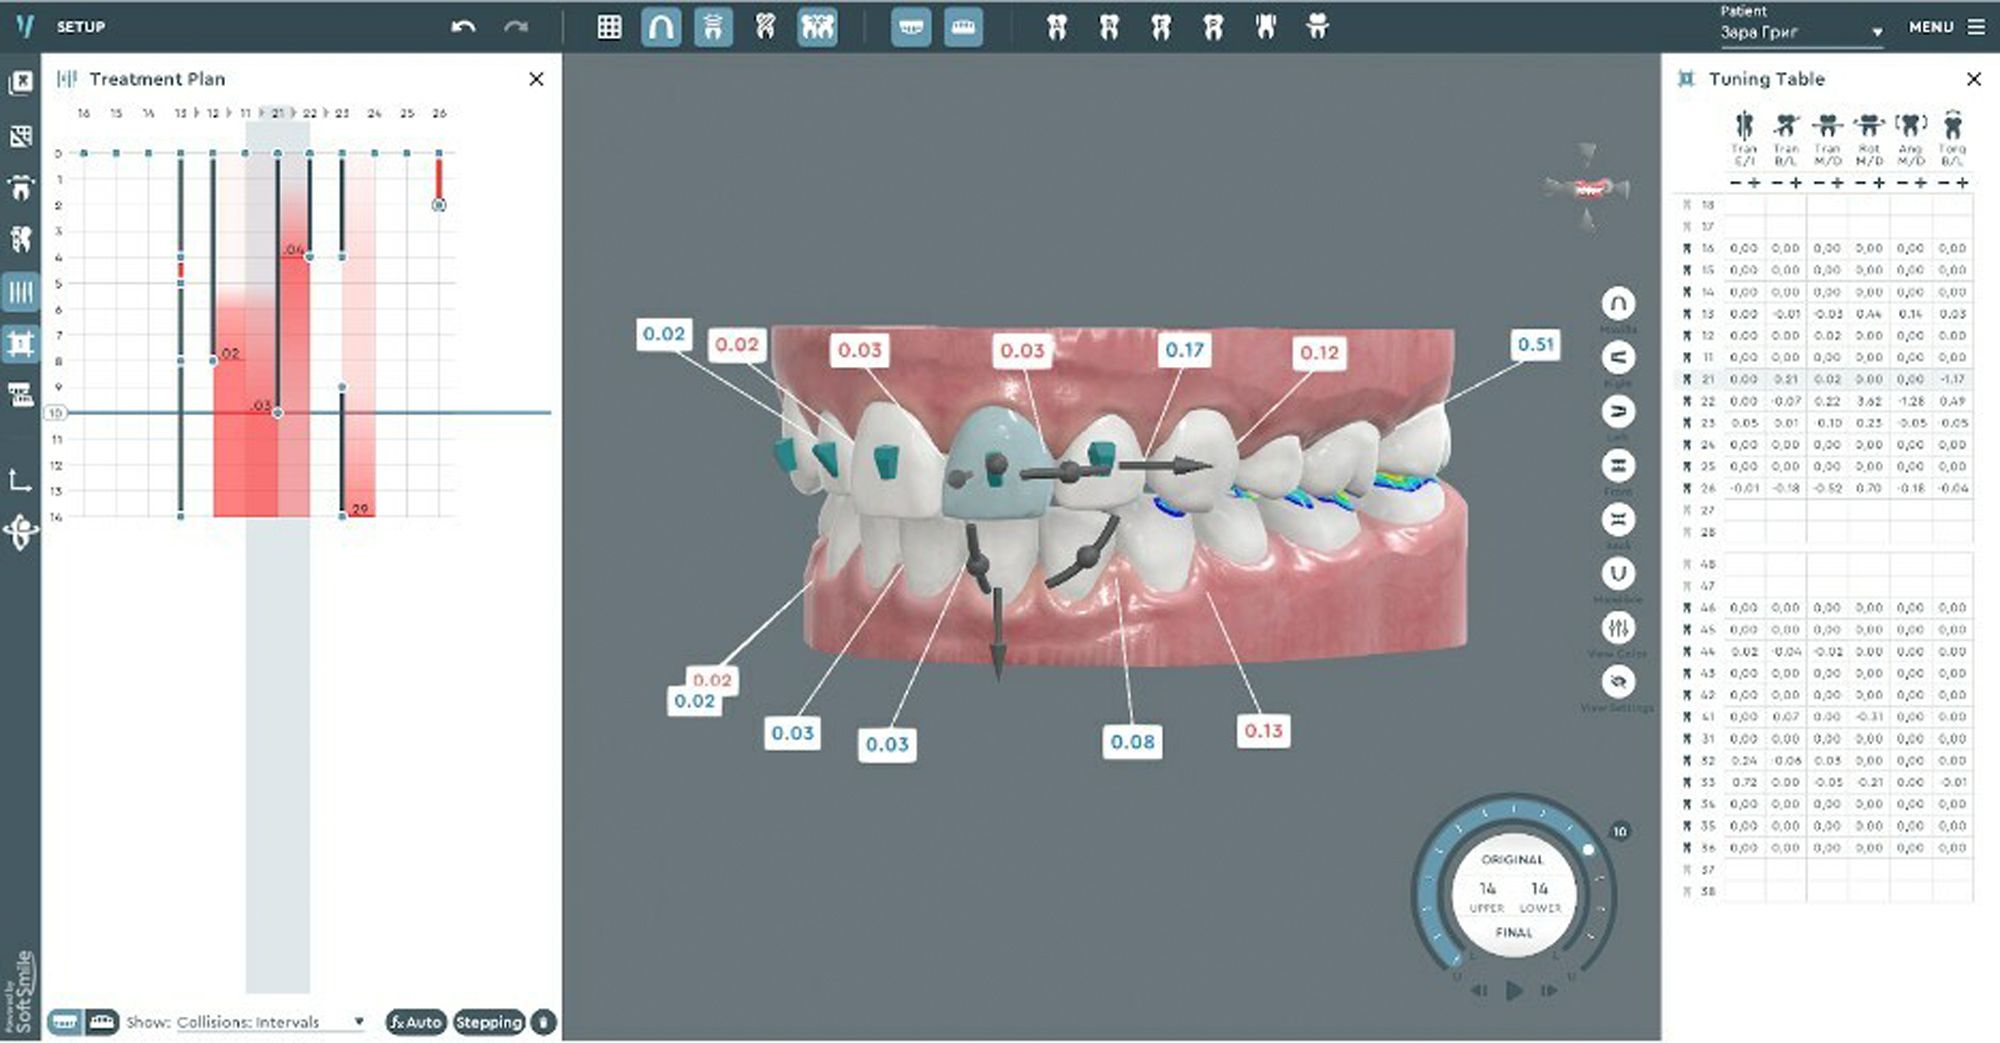

Planmeca Romexis® Smart are artificial intelligence (AI) tools for its Planmeca Romexis software platform. The feature allows the segmentation and recognition of anatomies, such as teeth, nerves, jaws, airways, and sinuses. This enables easier and faster use of the software and excellent visualization of the case for patient education. With the help of AI, CBCT images and intraoral scans are automatically mapped. Thanks to the automatic tooth number recognition, a CBCT volume can be easily navigated just by clicking on the tooth number in the tooth chart, and the software centers all views on the tooth of interest.